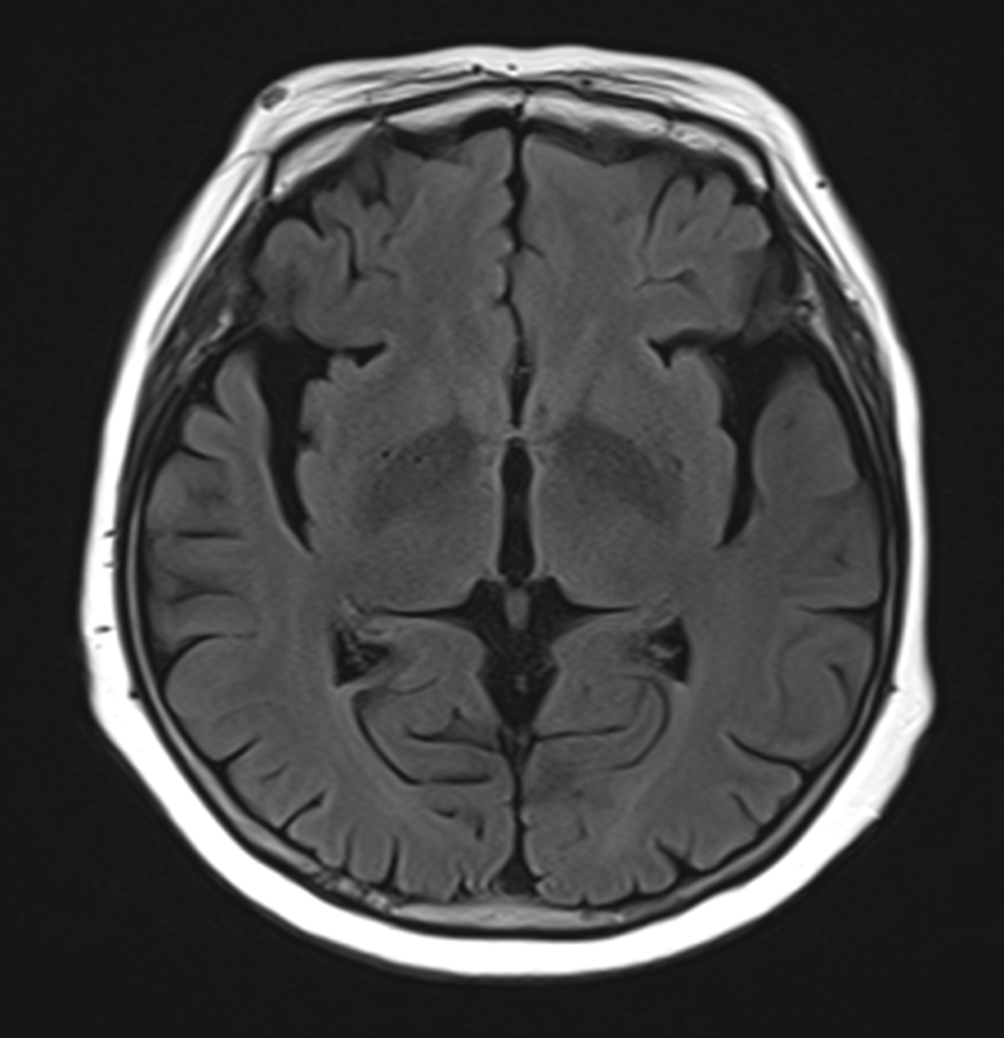

그림10.png 촬영 일시: 2025.12.23

<Fig 1. 뇌 MRI>

각종 검사 결과, 의심이 맞았어요.

파킨슨병 관련 질환이 강하게 의심되는 상황이었거든요.

추가 검사를 진행했고...

결과적으로 파킨슨증후군 진단을 받게 되셨습니다.